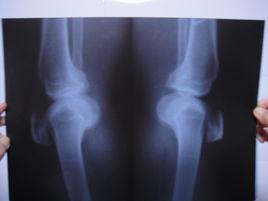

膝關節腫脹,關節積液,晨僵及久坐後有膠著現象,關節伸屈功能障礙,跛行,功能受限,伸屈活動有彈響聲,在下台階、久立時膝關節症狀加重,部分患者可見關節積液,局部有明顯腫脹、壓縮現象,膝其中關節前內側條索樣腫塊伴伸膝障礙,膝關節周圍骨贅形成,關節周圍伴有骨質疏鬆與骨質硬化。關節面毛糙不平,其內側脛股關節面受累明顯,關節間隙變窄,其中多數會發生內側間隙狹窄,髕骨骨刺形成。

膝蓋骨質增生膝關節骨質增生為臨床常見病、多發病,多發於中老年以上患者。臨床以雙膝關節劇烈疼痛、行走無力、活動受限、X檢查示雙膝關節骨質增生為特徵。本病手術適應證要求較高,且效果不好,給治療帶來了很大的困難。